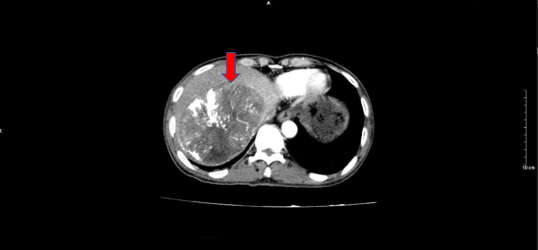

Tháng 5/2023 bệnh nhân vào viện vì đau bụng âm ỉ, ăn kém, buồn nôn nhiều, sút 5 kg/tháng, vào viện được chụp CT ổ bụng thấy có hình ảnh khối u gan phải kích thước 25x35mm, giảm tỷ trọng, không ngấm thuốc sau tiêm, khối u lớn kích thước 97x145mm chiếm gần toàn bộ gan trái có tính chất của HCC.

Hình 1. Hình ảnh chup CT ổ bụng có khối  u gan (sau điều trị TACE): khối lớn tái phát gan trái có tính chất động học của ung thư biểu mô tế bào gan (HCC). Khối gan phải không ngấm thuốc  (mũi tên đỏ).